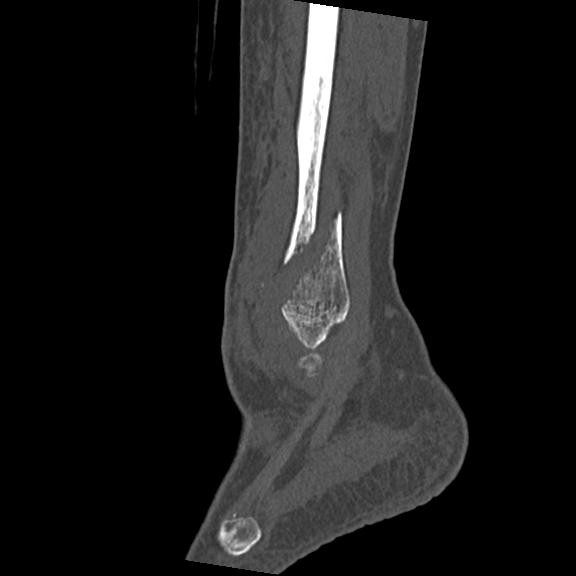

56476 8/28 4R 1/21 2R 左足関節 デジカメ写真 72歳女性 右足関節AS